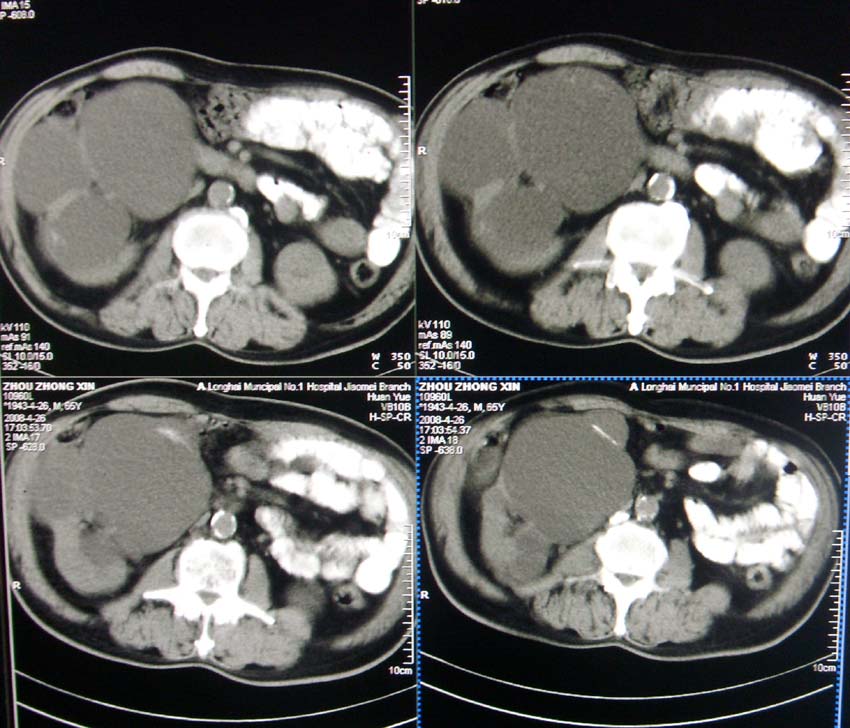

以下是引用liangshusheng在2008-4-27 13:28:00的发言:[br]双肾都有结石,右肾积水波浪状,输尿管积水,建议往下扫

以下是引用zjzjr在2008-4-27 14:25:00的发言:[br]1,右侧多发囊性占位,考虑囊肿可能大。[br]2,肾下部输尿管走行区囊性占位,巨输尿管?建议mru。